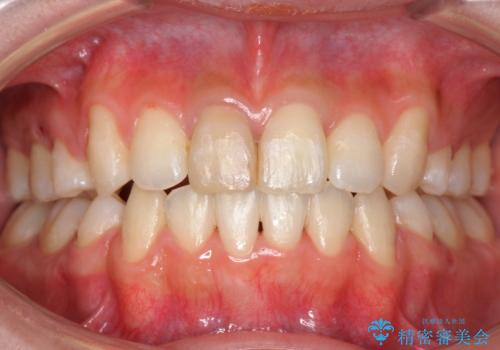

八重歯 前歯のがたがた 抜歯してワイヤー矯正

上下左右の小臼歯を抜歯し、ワイヤー矯正を行いました。

右上の前歯は変色もあり、神経の治療後にセラミックを被せる予定です。